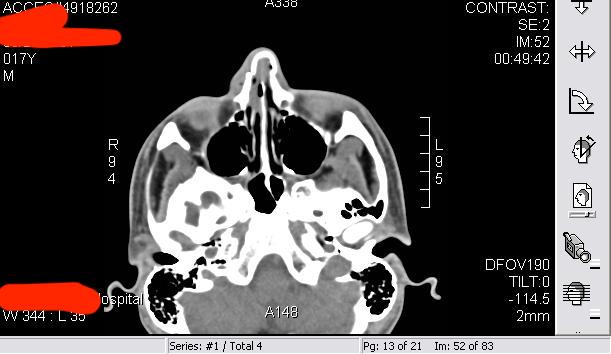

I got assaulted by a gang of urban youths when I was 17 and woke up in a puddle of blood; caved in left cheekbone as well.